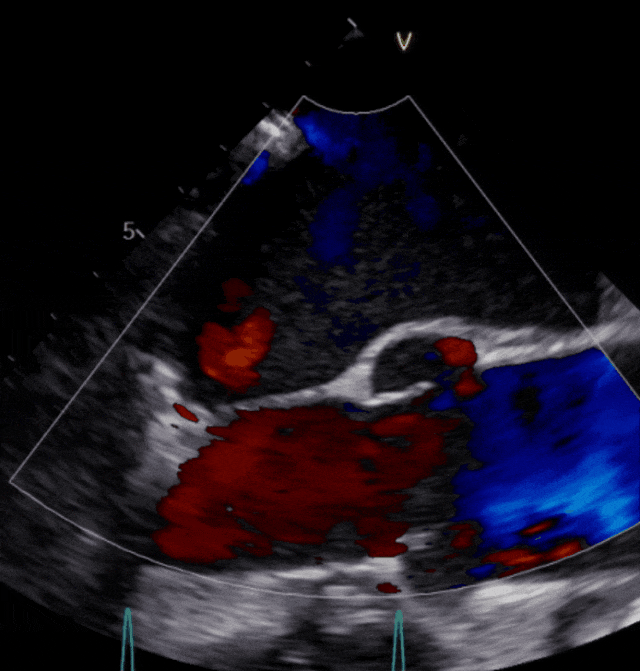

患者邵爷爷今年70岁,发现心脏瓣膜问题后辗转多地医院就诊未果,在昆山市中医医院经超声心动图检查,评估为二尖瓣重度反流。

图片

▲患者术前超声影像

患者二尖瓣3区前叶脱垂,脱垂宽度13mm,瓣口面积5.6cm2,平均跨瓣压差1.3mmHg。术前评估病人情况后决定采取策略在反流最大处植入一枚到两枚XTR或NTR,降低反流。